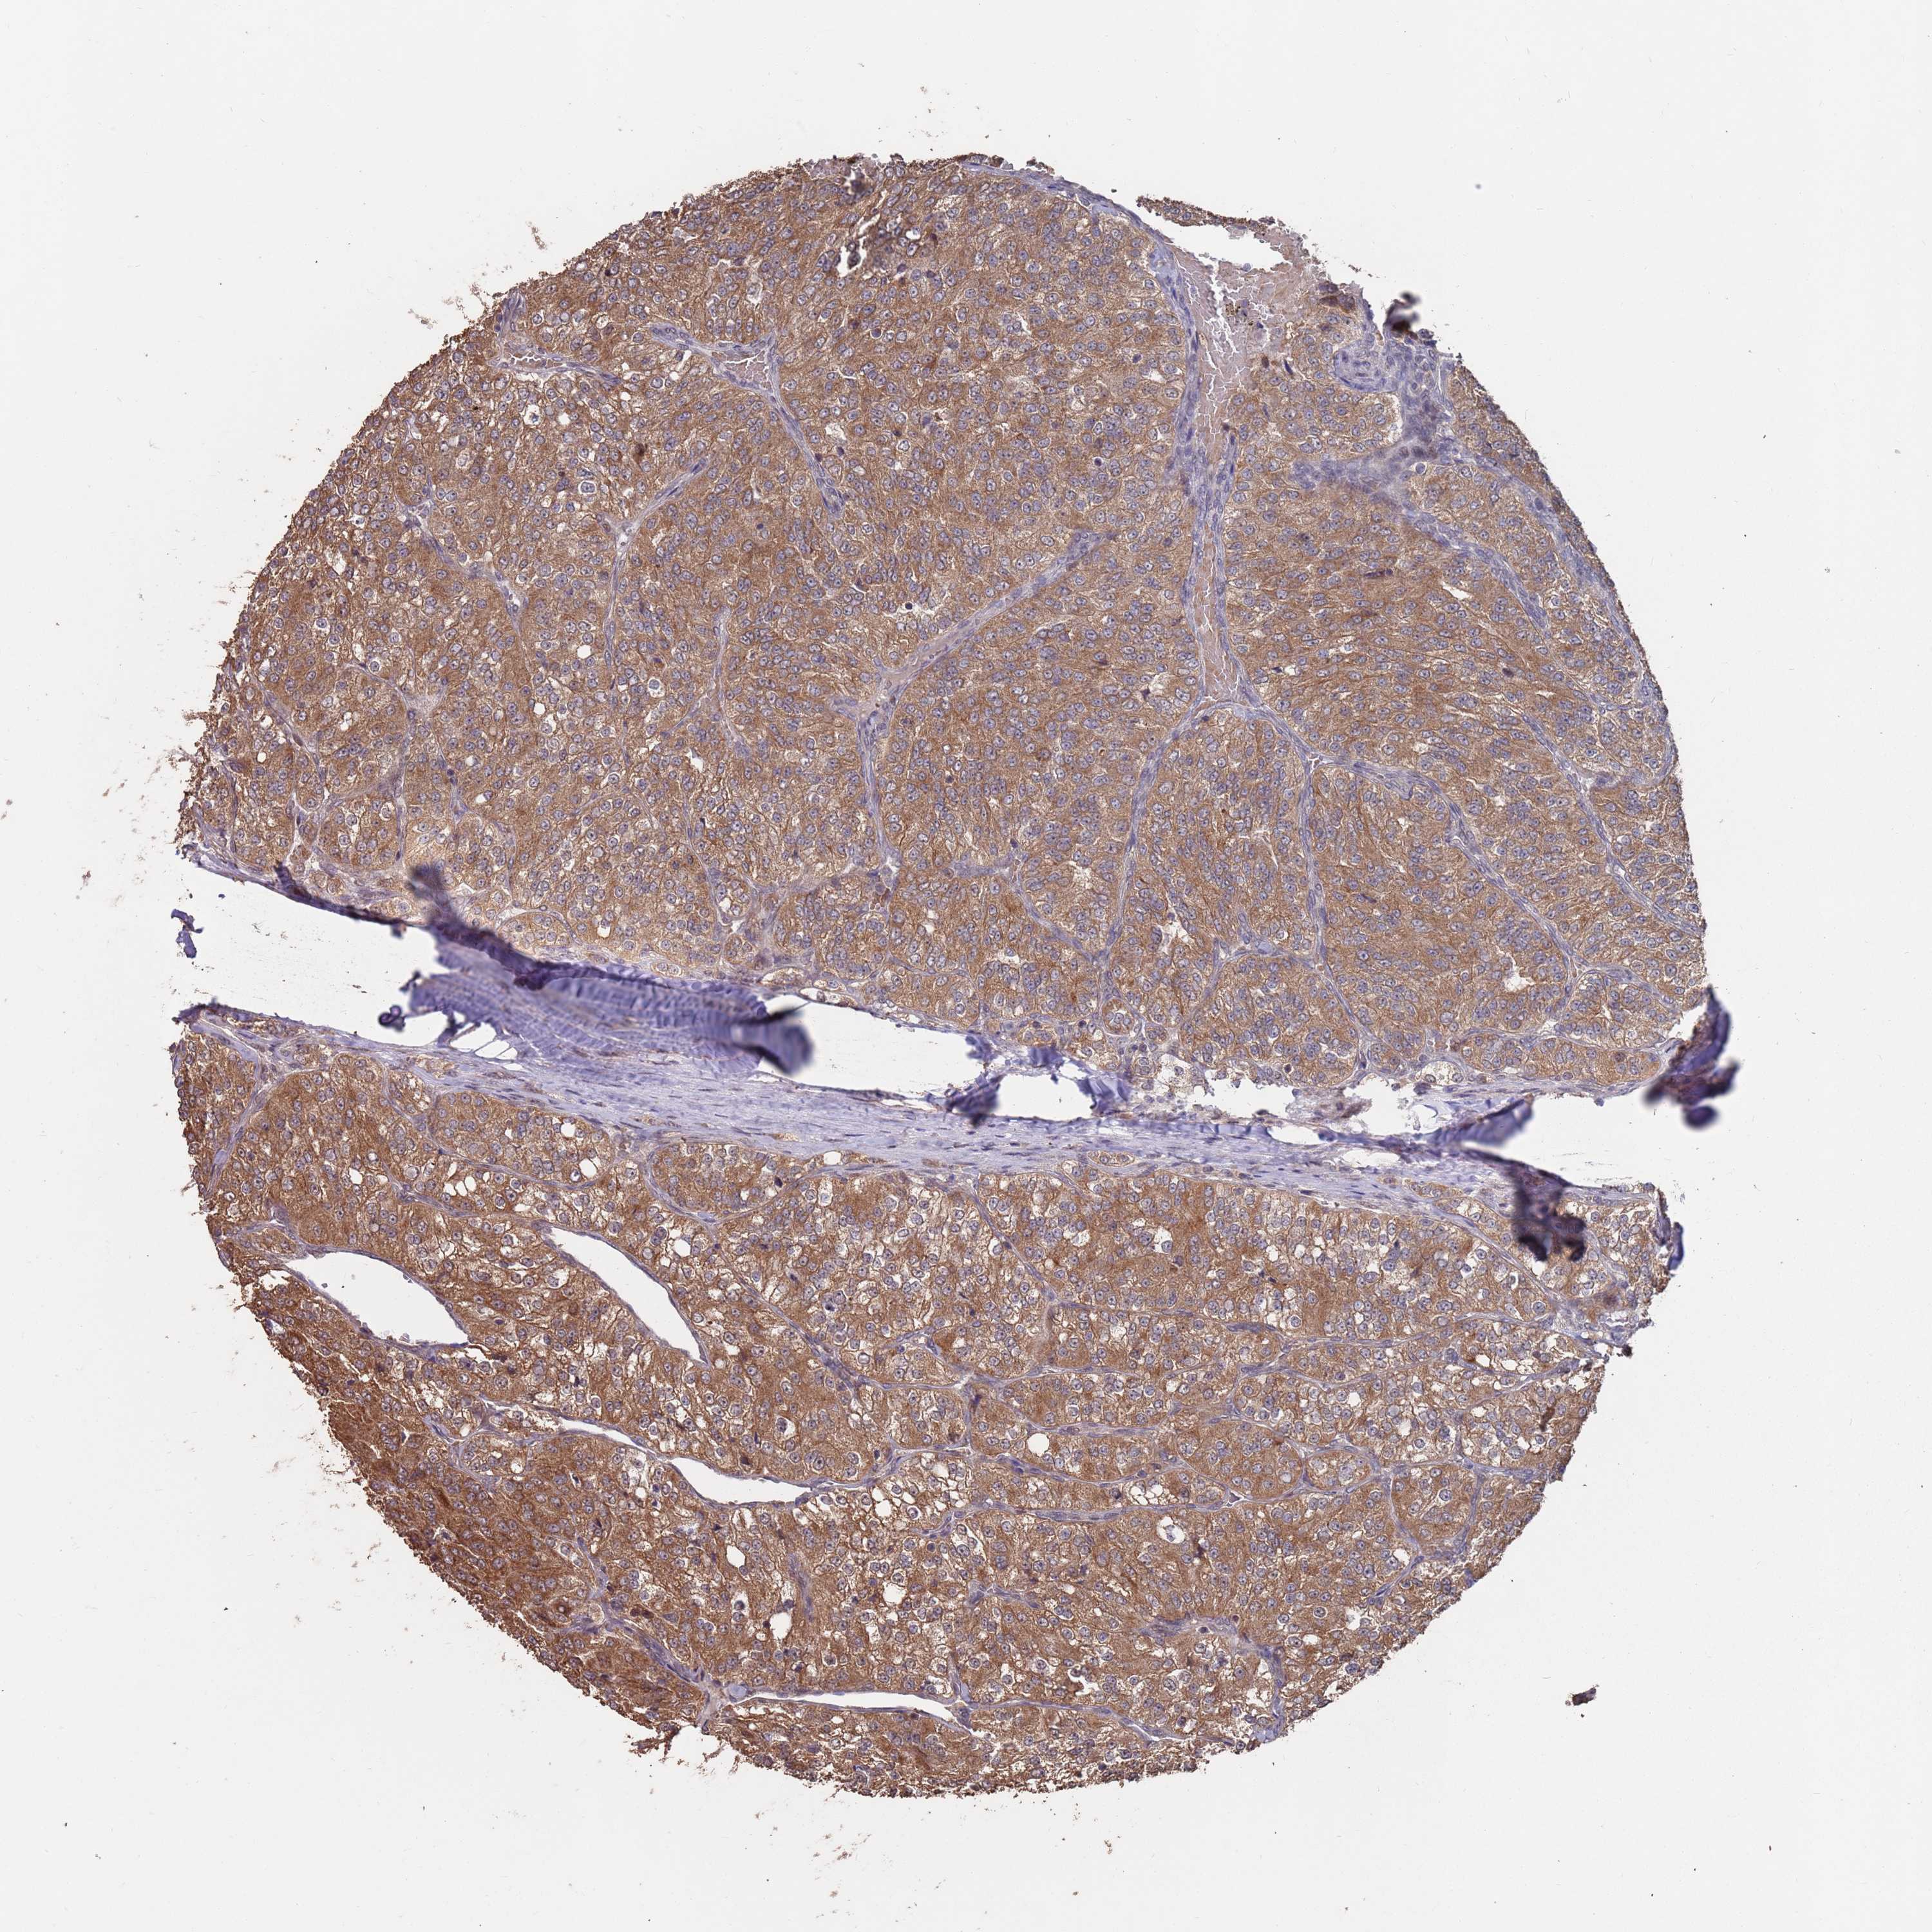

KIDNEY RENAL CLEAR CELL CARCINOMA (VALIDATION) - Interactive survival scatter ploti

The Survival Scatter plot shows the clinical status (i.e. dead or alive) for all individuals in the patient cohort, based on the same data that underlies the corresponding Kaplan-Meier plots. Patients that are alive at last time for follow-up are shown in blue and patients who have died during the study are shown in red.

The x-axis shows the expression levels (FPKM) of the investigated gene in the tumor tissue at the time of diagnosis. The y-axis shows the follow-up time after diagnosis (years). Both axes are complimented with kernel density curves demonstrating the data density over the axes. The top density plot shows the expression levels (FPKM) distribution among dead (red) and alive patients (blue). The right density plot shows the data density of the survived years of dead patients with high and low expression levels respectively, stratified using the cutoff indicated by the vertical dashed line through the Survival Scatter plot. This cutoff is automatically defined based on the FPKM cutoff that minimizes the p-score. The cutoff can be changed by dragging the vertical line or by entering a cutoff value in the square labeled "Current cut-off".

Under the Survival Scatter plot the p-score landscape (black curve; left axis) is shown together with dead median separation (red curve; right axis). Dead median separation is the difference in median mRNA expression between patients who have died with high and low expression, respectively. It is calculated as follows: median FPKM expression of dead patients with high expression - median FPKM expression of dead patients with low expression. This is intended to aid the user in visually exploring custom cutoffs and the associated p-scores and dead median separation.

Individual patient data is displayed and can be filtered by clicking on one or more of the category buttons on the top of the page. Categories describing expression level and patient information include: high, low, alive, dead, female, male and tumor stages. The scale of the x-axis can be toggled between linear and log-scale by clicking on the "x log" button. Mouse-over function shows TCGA ID, patient information and mRNA expression (FPKM) for each patient.

& Survival analysisi

Kaplan-Meier plots summarize results from analysis of correlation between mRNA expression level and patient survival. Patients were divided based on level of expression into one of the two groups "low" (under cut off) or "high" (over cut off). X-axis shows time for survival (years) and y-axis shows the probability of survival, where 1.0 corresponds to 100 percent.

PRR7 is not prognostic in Kidney Renal Clear Cell Carcinoma (validation)

Best expression cut offi

Based on the FPKM value of each gene, patients were classified into two groups and association between prognosis (survival) and gene expression (FPKM) was examined. The best expression cut-off refers the FPKM value that yields maximal difference with regard to survival between the two groups at the lowest log-rank P-value. Best expression cut-off was selected based on survival analysis .

When clicking on this number, the vertical dashed line indicating cut-off, the interactive survival plot, and the Kaplan-Meier curve will be adjusted to show results based on the best expression cut-off.

: 12.93

P scorei

Log-rank P value for Kaplan-Meier plot showing results from analysis of correlation between mRNA expression level and patient survival.

N/A

TCGA RNA samplesi

RNA-seq data is reported as average FPKM (number Fragments Per Kilobase of exon per Million reads), generated by the The Cancer Genome Atlas (TCGA) .

Normal distribution across the dataset is visualized with box plots, shown as median and 25th and 75th percentiles. Points are displayed as outliers if they are above or below 1.5 times the interquartile range. FPKM values of the individual samples are presented next to the box plot.

Average pTPM 11.3

Number of samples 100